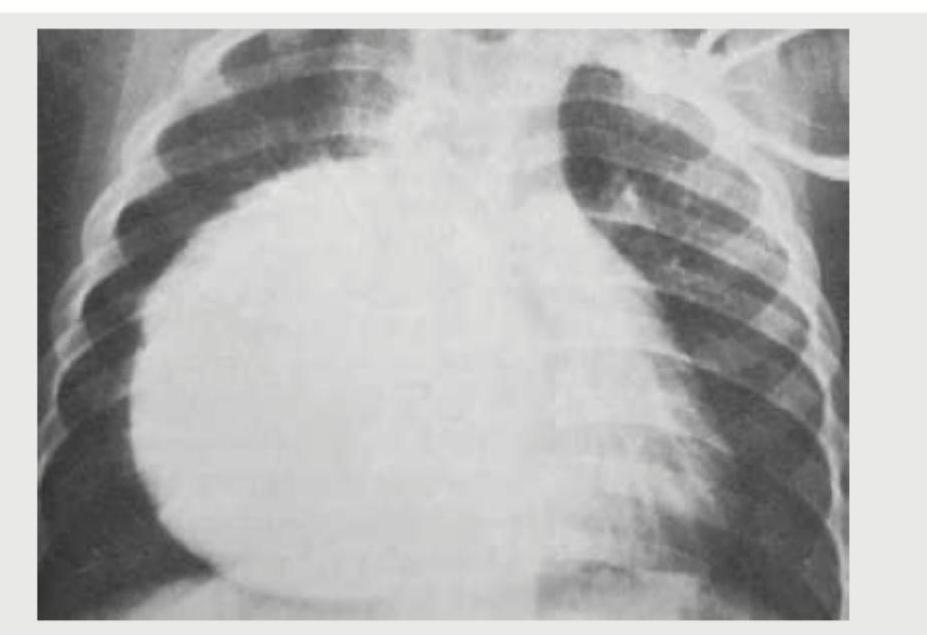

In the chest X-ray shown, identify the chamber enlargement:

In the chest X-ray shown below, identify the chamber enlargement:

A 30-year-old hypertension patient presents with daily headaches. The CXR given below shows which of the following? (Recent NEET Pattern 2016-17)

Identify the chamber enlargement:

Explanation: ***Left atrium*** - The chest X-ray shows **double contour sign**, an increased **carinal angle**, and **elevation of the left main bronchus**, all classic signs of **left atrial enlargement**. - The convexity of the left heart border appears straightened, and there might be a "bulge" or straightening of the **left cardiac border**, further indicating left atrial enlargement. *Right atrium* - Right atrial enlargement would typically show a prominent **convexity of the right cardiac border** extending further to the right. - This image does not demonstrate significant prominence or bulging of the right heart border beyond what is expected. *Left ventricle* - Left ventricular enlargement usually presents as increased **cardiac apex prominence** and **downward displacement** of the cardiac apex. - While there is some cardiomegaly, the primary signs visible (double contour, carinal angle change) point more specifically to left atrial enlargement. *Right ventricle* - Right ventricular enlargement typically manifests as **increased prominence of the right ventricle** along the left heart border and an **uplifted cardiac apex**. - No clear evidence of right ventricular specific enlargement signs like severe right heart border prominence or uplifted apex is seen here.

Explanation: ***Left ventricle*** - The image shows **cardiomegaly** with a markedly enlarged heart shadow, particularly extending to the **left and inferiorly**. This is characteristic of severe **left ventricular enlargement**. - In cases of substantial left ventricular dilatation, the cardiac apex shifts downwards and to the left, often pushing the hemidiaphragm inferiorly, as appears to be the case here. *Right atrium* - **Right atrial enlargement** typically presents as prominent fullness or bulging of the **right heart border** on a chest X-ray. - While it can contribute to cardiomegaly, the dominant projection and extreme size seen here are more indicative of a ventricular chamber. *Right ventricle* - **Right ventricular enlargement** can cause the heart to appear enlarged, often with elevation of the **cardiac apex** or an increase in the retrosternal clear space on a lateral view. - On a PA view, significant right ventricular enlargement can push the left ventricle posteriorly and cause a rounding of the cardiac apex, but the extreme leftward and inferior extension points away from isolated right ventricular enlargement. *Left atrium* - **Left atrial enlargement** is typically identified by an enlarged **left atrial appendage** on the left cardiac border, a **double density sign** (due to the right border of the enlarged LA), or splaying of the carina. - While left atrial enlargement often accompanies left ventricular issues, the overall massive increase in heart size, especially laterally and inferiorly, suggests primary ventricular enlargement rather than isolated or dominant left atrial enlargement.

Explanation: ***Postductal coarctation*** - The image shows **rib notching** (highlighted by the arrow), a classic sign of **collateral vessel development** due to narrowing of the aorta **distal to the ductus arteriosus**. - This congenital heart defect is associated with **hypertension** in the upper extremities and can lead to symptoms like **headaches**. *Preductal coarctation* - This typically presents earlier in life, often with **heart failure** in infancy, and is less commonly associated with **hypertension** and **rib notching** in a seemingly asymptomatic adult. - The coarctation is located **proximal to the ductus arteriosus**, leading to different collateral circulation patterns. *Aortic dissection* - This condition is an acute medical emergency characterized by a tear in the **aortic wall**, often presenting with sudden, severe chest or back pain. - CXR findings typically include a **widened mediastinum**, not specifically rib notching. *Takayasu arteritis* - This is a **granulomatous vasculitis** primarily affecting the aorta and its major branches, leading to narrowing or occlusion. - While it can cause hypertension, **rib notching** is not a characteristic radiological finding; signs usually include vessel wall thickening or stenoses.

Explanation: ***Left atrium*** - The chest X-ray shows **cephalization of the pulmonary vessels** and a **double contour sign** over the right heart border, indicating left atrial enlargement. - There is also evidence of **pulmonary congestion** and **interstitial edema**, consistent with elevated left atrial pressure. *Left ventricle* - Left ventricular enlargement would typically manifest as **cardiomegaly** with a **leftward and downward displacement of the apex**. - While there is some cardiac enlargement, the specific signs for left atrial enlargement are more prominent. *Right atrium* - Right atrial enlargement would typically show a **prominent right heart border** that extends further to the right. - This is not the dominant feature seen in this X-ray. *Right ventricle* - Right ventricular enlargement would shift the **cardiac apex superiorly**, forming a "boot-shaped" heart, or cause a **prominent outflow tract** on lateral views. - The findings here are more consistent with left-sided heart chamber issues affecting the pulmonary circulation.